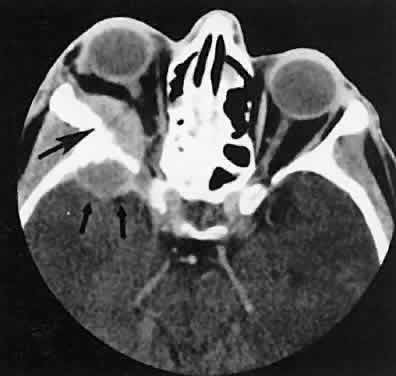

Perhaps the most common intracranial tumor to extend into the orbit is the meningioma. Those located along the spheroid wing tend to be associated with hyperostosis and tumor infiltration of the posterior lateral wall and roof of the orbit (Fig. 20). In our experience, isolated enlargement of the lateral rectus muscle is never caused by Graves' orbitopathy but rather is secondary to infiltration by spheroid wing meningiomas.

Fig. 20. Axial scan of a sphenoid wing meningioma showing an enhancing intracranial component (small arrows) with intraorbital extension. Note reactive hyperostosis of the sphenoid bone (large arrows).